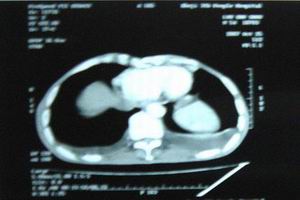

3.甲狀旁腺功能減退症因腦組織鈣化可出現錐體外系症狀,如不自主運動、手足徐動、扭轉痙攣、震顫、小腦共濟失調、步態不穩等,易被誤診為神經系統病變。應仔細觀察有無低鈣血症及其相應的臨床表現,同時採用X線或CT檢查腦組織鈣化病變,將有利於甲狀旁腺功能減退症的診斷。

2.影像學檢查頭顱X線攝片約有20%顯示基底節鈣化,少數病人尚有松果體及脈絡叢鈣化;CT掃描較之X線攝片更敏感,能更早及更多地發現顱內鈣化灶。

甲狀旁腺功能減退症2.癲癇樣發作及其他神經症狀表現除了觀察低鈣血症及其臨床表現外,用X線或CT檢查腦組織鈣化病變,對診斷很有幫助。